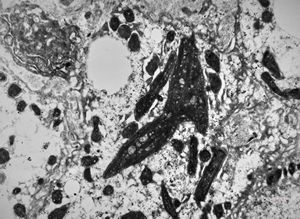

M,58y. | crystalline inclusions in hepatocyte after unknown medication